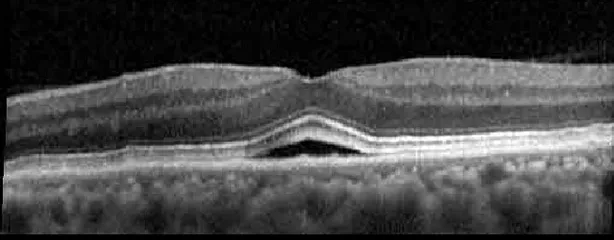

Figure 1

The patient began treatment with oral pemigatinib daily and was followed up for an ophthalmic examination during the second treatment cycle approximately 5 weeks into the treatment process. The patient had at this stage received 28 doses of 13.5 mg per day, which was administered in cycles of 14 on-days and 7 off-days, and had no visual or ophthalmic complaints. The non-corrected VA was OD 20/30 + 1 and OS 20/20. The OCT examinations revealed subfoveal SRF bilaterally. The fundus examination was otherwise unremarkable outside the patient’s prior documented peripheral drusen. Repeat autofluorescence was overall unchanged, though a slight hypofluorescent ring may be visualized in Figure 2. The current pemigatinib protocol recommendation for asymptomatic patients suggests no dose modification; however, with worsening presentation or positive symptoms, it is recommended to withhold pemigatinib. After discussion with the patient’s oncologist, it was decided to continue the medication at this time. Serial monitoring of the patient’s symptoms, vision, and SRF were conducted on specific days during active treatment cycles and days off-cycle to monitor the SRF. Subsequent evaluations demonstrated complete resolution of SRF while off-cycle, and asymptomatic re-accumulation of fluid while on-cycle with varying levels of VA. (Table 1) As we see demonstrated in the table below, in the later stages of the active cycles, such as day 13 of 14 of cycle 2, day 13 of 14 of cycle 3, day 13 of 14 of cycle 4, and day 14 of 14 on cycle 5, the patient’s VA showed no correlative changes based on the presence of SRF. The fluctuations in the patient’s VA certainly occurred, but were likely to be secondary to surface changes, as certain off-cycle days actually presented with lower acuities than days when the SRF was present on OCT examination.

Table 1

| Cycle, day, on/off | VA OD; OS | CMT OD; OS | OCT OD | OCT OS |

| Prior to initiation | 20/40; 20/20−2 | 274; 275 | ![]() | ![]() |

Highlights the visual acuity, central macular thickness, and the physical OCT of the macula for this patient in both the right and left eyes during various stages of the patient's chemotherapy treatment cycle.